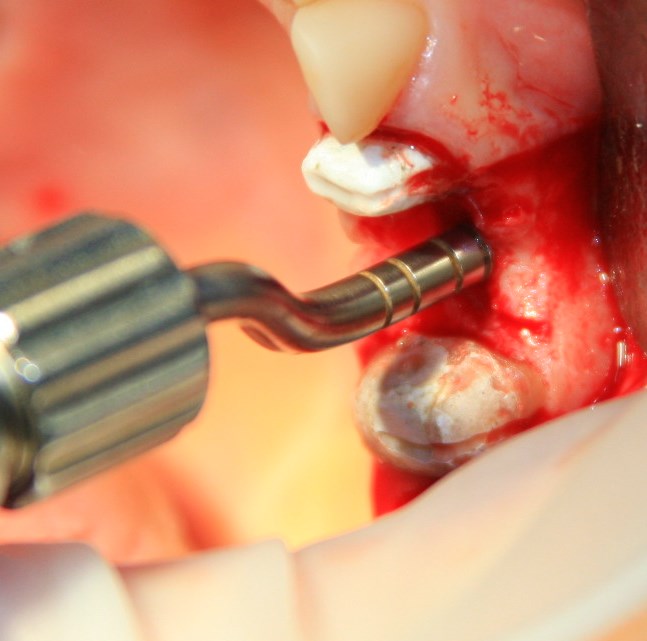

В данном случае я использовал Geistlich Mucograft Seal 8mm. Биоматериал в данном форм-факторе стоит дешевле, чем барьерная мембрана, а его диаметр позволяет легко перекрыть образовавшийся дефект слизистой:

Перед позиционированием Mucograft лучше намочить. Он станет более эластичным (без потери прочности) и мягким:

После чего, он легко приклеивается и перекрывает дефект: